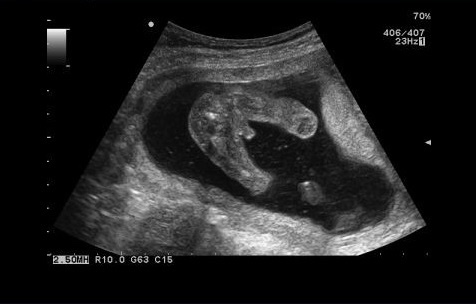

Девочки чуйка не подводит ( знала ) , прошла первый скрининг на 11,4 дня, пол сразу сказали , узи у инякина , понравилось четко ясно 😀первый раз в жизни у мужчины прошла😱😂

Это получается мальчик сидит ,тянет руки вперёд и писюн видать да же ?)

Девочки объясните 🙈 то что по середине торчит как бы это и есть достоинства его?🤪😁

Ну уже человечке прям , это видео через узи вагинально ☺️

Мне в 12 недель тоже сказали пол 100%😊 в 10-й поликлинике была на учёте, врач Наби👍Такую же картину наблюдала через экран 🥰🥰 Врач сказал мальчик, а вот писюнчик☺ Я как давай реветь, первый раз своего сыночка увидела через экран 😭😭😭💙💙💙 а сейчас на руках у меня, сиську сосет и засыпает😴 Мой 👼

Это он на попе сидит? Разложил так аккуратно яйки 😁